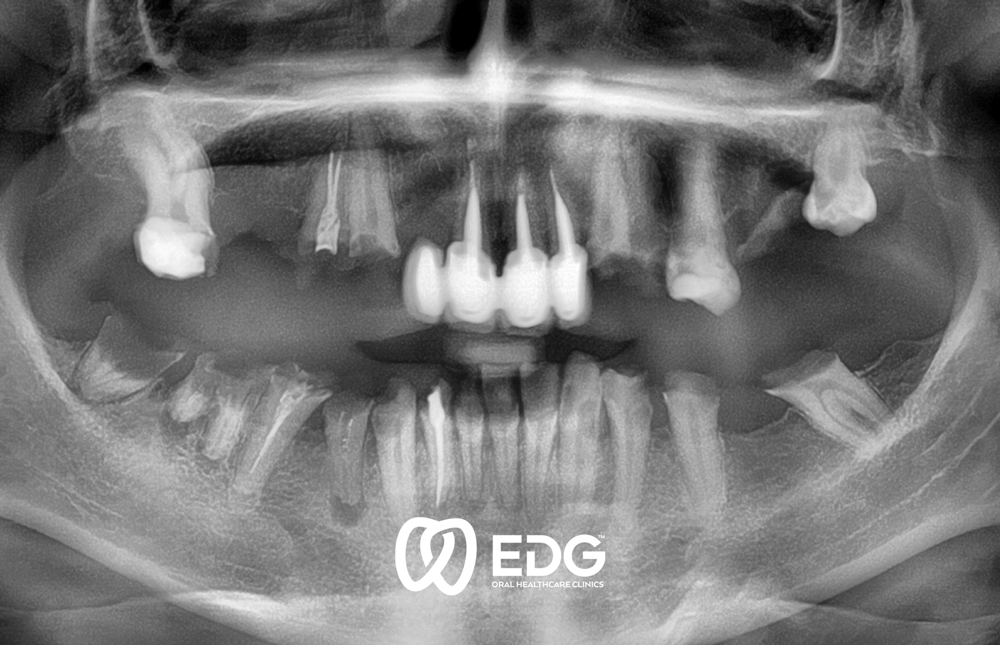

The loss of a tooth can be due to various reasons: caries, periodontitis or injuries and accidents. We offer our patients up-to-date care which brings in line aesthetic and functional standards and individual requirements. We insist on the inseparable connection between the form and function of dental prosthetics. Only functionally good work leads to good aesthetic results. For the selection and manufacture of the dental prosthesis, objective criteria play a part as well the patient type and the patient’s age. The complex prosthodontic reconstruction of the dentition requires a precise and extensive diagnosis before reconstructive measures can be started. To do this, a thorough medical anamnesis is necessary, as well as radiodiagnostics and the use of modern methods to exactly determine the position of the teeth and the movement of the temporomandibular (jaw) joint. For prosthodontic restoration, we use modern crown and bridge technology, partial and full prostheses and implants.